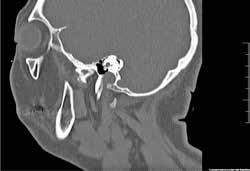

Para completar el estudio, se solicitó una tomografía axial computoriza da craneofacial (TAC) (Figura 1), dónde tras un examen exhaustivo a través de distintos cortes y reconstrucción 3D, evidenciamos una anquilosis de la ATM a la base de cráneo, desapareciendo por completo la anatomía nor mal de la ATM y su relación habitual con las distintas estructuras neurovas culares, así como la gran deformidad esquelética resultante del crecimiento y desarrollo craneofacial anormal.

Gracias a esta planificación, se logró una mayor precisión en los movi mientos quirúrgicos, una mayor predictibilidad y reproducción, una dismi nución de los riesgos quirúrgicos por mediciones de estructuras anatómicas concretas (como la arteria carótida interna, el nervio facial, el nervio man dibular, la arteria maxilar interna…) (Figura 1) y un menor tiempo operato rio, entre otras ventajas.

Figura 1. Diagnóstico prequirúrgico del bloque anquilótico. Imágenes TAC en 3D, corte axial y corte sagital..